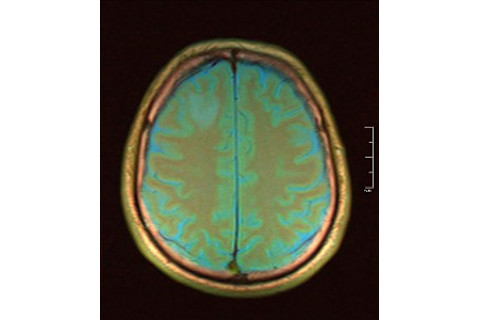

This idea, to any reasonable observer, would seem like something beyond "The Matrix," beyond the surrealism depicted by a Dali painting, beyond the wildest imaginable work of science fiction. And yet, the physicists and cosmologists who have been contemplating and advocating such a bizarre picture of reality are among the most renowned and include names such Alan Guth of MIT, Leonard Susskind of Stanford, and Sean Carroll of Caltech (who writes a blog for this magazine; his blog post on this very idea can be found here). So, what is a "Boltzmann brain"? Ludwig Eduard Boltzmann (1844-1906) was an Austrian physicist who pioneered statistical mechanics and derived the famous equation for the entropy (or degree of disorder) of a system: S = k log W, where S is entropy, k is Boltzmann's constant, log is the natural logarithm, and W is the frequency of occurrence of a macrostate of the system (such as pressure or temperature). The second law of thermodynamics implies that the entropy---the degree of randomness, or disorder---of any closed system never decreases (and generally increases). To better understand randomness and entropy---and to get a feel for why entropy naturally increases---think of a child's room that is neat and orderly at the beginning. Then the children come in and play, and afterwards you always find complete chaos: the electric train tracks are strewn all over the carpet, there is a toy truck upside down, a couple of dolls have been randomly thrown on the floor, and a chair is lying on its side. Then the child's mother comes into the room and expends energy (perhaps 20 calories, equivalent to running on your treadmill for 2 minutes) to restore order to the room. Energy and entropy are indeed related concepts---as we see here through the fact that investing energy can bring back order to the system and thus reduce its entropy. So a high-entropy state is "normal," while creating order is something that requires concentrated, directed energy. This is an important observation. Boltzmann wondered why our observed universe seems so orderly rather than completely random, as one might expect as the "natural" state of the universe. He obviously was never stuck in rush-hour traffic in Manhattan, or downtown Taipei or Tel Aviv. And he hypothesized that perhaps our portion of the universe is just a statistical fluke: an aberration within a wider universe in which randomness reigns supreme. So a Boltzmann brain, named after him, is a brain--a conscious observer--that materializes out of the disorderly universe purely by chance (a very, very small chance, I must emphasize) in the same way that, as Boltzmann had suggested, our entire universe may have emerged out of a wider chaotic multiverse purely through a random event. As Andrei Linde of Stanford put it in an interview with the New York Times: "It's cheaper" to create just a disembodied brain than it is to make a universe. But is it, really? Connecting to the Higgs boson I will come back to this question shortly, but first I want to talk about the Higgs boson. What does it take to "create" a single subatomic particle, a Higgs boson? If you've followed the story of the search for the Higgs, which culminated with great excitement in a press conference at CERN, near Geneva, Switzerland, on July 4th of this year when the Higgs discovery was announced, then you know a few things. You know that it takes expending an energy that is equivalent to the entire electric power consumption of a city the size of Geneva, running continuously for several years in a highly concentrated way---many trillions of protons are accelerated to close to the speed of light and then directed very precisely to crash into other protons---just to create a few Higgs bosons. And the Higgs is highly ephemeral: it lives for a tiny fraction of a second--something like 0.0000000000000000000007 seconds. Then it decays into other particles. The reason that the Higgs lives for only such a minuscule fraction of a second is the celebrated Heisenberg's Uncertainty Principle. According to this principle, there is a quantum-mechanical constraint on the product of time and energy. Since the Higgs has a mass that is equivalent to an energy of 125.3 GeV (billion electron volts), it can only live for a very small fraction of a second. (A muon, on the other hand, can live much longer---for 2.2 millionths of a second---because its mass-energy is much smaller.) Now back to the Boltzmann brains: The proponents of cosmic inflation, Alan Guth (who first proposed the theory in 1980) and Andrei Linde and Alex Vilenkin (who both independently argued that inflation is eternal), have come to the conclusion that the multiverse must exist because the inflationary process undergoes quantum fluctuations. So even though the inflation that worked its magic on our universe ironing out any primeval "kinks" to create the "flat," or mathematically Euclidean universe we see today seemed to come to a stop, it never did. It just went elsewhere. It is now doing its trick on infinitely many other universes. These three physicists (together with Andrea de Simone of MIT, Mahdiyar Noorbala of Stanford, and Michael P. Salem of Tufts) recently wrote an article that attempted to set some bounds on the number of Boltzmann brains in the multiverse and the spacetime volume of the multiverse. But the existence of both Boltzmann brains and an infinite multiverse rely on probability theory within the context of the deep mathematical concept of infinity. And physicists have traditionally had a very uneasy relationship with infinity. At least eight extremely gifted individuals have been awarded Nobel Prizes in physics for the great achievement of removing infinities from physical theories! These are Richard Feynman, Julian Schwinger, and Sin-Itiro Tomonaga; Gerardus 't Hooft and Martinus Veltman; and Frank Wilczek, David Gross, and H. David Politzer. Infinity has until recently been the scourge of theoretical physics, and the people mentioned above have established various quantum field theories--essential to modern physics--by ingenious and painstaking work of making infinite answers (which physicists consider completely nonsensical) disappear from calculations. This task is called "renormalizing a theory." But now, after Linde and Vilenkin have argued that inflation must be eternal (and string theory and the "many worlds" approach also imply the existence of other universes), infinity has wiggled its way into physics in a seemingly positive way. But infinity is a nasty, unwieldy idea. There is good reason to try to purge it from physical theories. Infinity and beyond Let me explain what I mean using the most familiar example I know: monkeys typing Hamlet. Monkeys don't type Hamlet, or anything, really. But suppose a monkey sits in front of a computer keyboard forever. The minute you talk about forever, anything at all is possible. The first trillion-trillion-gazillion attempts lead to nothing: just garbage of letters being typed randomly. Then, by chance, the monkey types: "Act one, Scene 1: Elsinore. A platform before the castle. Enter Barnardo and Francisco, two Sentinels." But then the monkey continues: "gsdft rhdfsrax uurlwtsc bzdw..." and you wait another googolplex of years, and you get back the real sentence above, plus--instead of the nonsense--"Barnardo: Who's there?" and then back to garbage. Of course, in between, the monkey also types the first sentence as I have it, except that "Elsinore" is typed as "Elsibore"--so no cigar; and so on, pretty much forever. The play has about 30,000 words, and if we assume an average of 5 letters per word, we have about 150,000 characters that the monkey needs to get right and in sequence. So the probability of getting it correctly the first time (leaving out spaces and punctuation, and special characters, which would make it even more difficult) is one divided by 26 raised to the power 150,000, which is a number very, very close to zero--but not identically zero. So, theoretically, as you "go to infinity," it will happen, but in reality you would have to wait an exceptionally long period of time (given any rate at which the monkey types), which could very well be "forever."* And there are theorems in the theory of probability where an event (a recurrence of a state, such as in a random walk or a Markov chain) will occur infinitely often--however, the waiting time for even the first recurrence can be proved to be infinite! This means that, yes, something can happen infinitely many times, but for it to occur the first time, you have to wait until "forever." How does this fact affect "infinity" considerations in the practical realm of physics? Mathematicians can talk about actual infinity (in addition to the potential infinities, appearing as limits in the calculus) because, to them, it has no application in the real world. What, in the real world, is truly infinite? The example I am showing you here demonstrates yes, if you "go to infinity"--whatever that means in the real world--you can "prove" almost anything you like! The monkey typing forever, meaning producing infinitely many replications of 26 characters, will theoretically produce not only the whole of Hamlet--in fact, the monkey will do it infinitely many times!--but also every piece of writing ever created in history, including all the works in the lost great library of Alexandria, as well as Virgil, Dante, Hemingway, Jane Austen, Salman Rushdie, and the U.S. Constitution; and every letter any person in history has ever written to another person, or would have written, or might write, or could write, or will ever write; and every possible grocery list, and every possible presidential election speech. You can see just how preposterous all of this becomes when you try to apply an abstract mathematical concept to the real world. And by the theorem I've alluded to, it may take "forever" for these things to happen. Back to Boltzmann But if you travel forever in the multiverse, will you encounter a single Boltzmann brain? The argument made by Linde (in the New York Times link above) and by Carroll (in his "Cosmic Variance" blog) as well as by other proponents of the infinite multiverse and its Boltzmann brains is that the probability of producing--purely by chance, through quantum fluctuations, in infinite space and time--a disembodied brain is higher than the probability of producing an entire universe. But this is not true. A brain requires a body to support it, and a world to feed it and house it and protect it, and--from everything we know so far from science--it needs 13.7 billion years of an expanding universe, galaxy and star formation, including many millions of years of fusion in stars to create and spread around the iron and carbon and oxygen and other essentials needed to start and maintain life on a hospitable planet, and to set evolution in motion, in order to create a conscious, thinking, self-aware brain. You might say that we don't really need a human brain--it can be a computer. It would have to be a very advanced computer--one with consciousness, which is something we haven't been able to make so far. But even so, it would still require the silicon chips, and the rare-earth metals, and the integrated circuits, and all the right electronic connections, and a power source, and everything would have to be put together in a precisely-specified way: or else it won't work. Wait to infinity and these ingredients will all just materialize in the right way through a "quantum fluctuation"? I think not. The case of a Boltzmann brain is unmeasurably more complicated, and astronomically more demanding probabilistically, than that of a simple sequence of 150,000 characters to be typed in the right order. It is, in fact--because of the requirements of something like our world to support a human or a computer brain--an event of probability zero. It cannot happen by itself even "at infinity." If you are not convinced, let's go back to the Higgs boson (I brought it up for a reason). I hope I've convinced you that even a single subatomic particle--to make it appear as a particle, rather than the field associated with the particle (the Higgs field permeates everything)--requires immense amounts of highly directed energy. Multiply that by an unimaginably large factor to create even a few atoms to be placed in the right spots (all of this happening by chance, through some "quantum fluctuation," as these physicists describe it) and you still have a fantastically long way to go to make an actual brain. My contention is that even infinity won't help you here, since the probability of a quantum fluctuation producing a complex entity such as a brain is zero. Ask yourself: What is the probability that a Large Hadron Collider would materialize out of the void, all by itself, with all its required highly concentrated energy, to produce even one particle? And for a brain we need an extremely ordered array of many particles. Recall that the Higgs lives for a very short time because of its mass. Suppose even that a Boltzmann brain can be small enough to be a quantum object, created through a quantum fluctuation in the vacuum. Its mass alone would cause a big problem. And here I come to the crux of my argument: By the Heisenberg Uncertainty Principle, this brain will live a lifetime that is far, far shorter than the tiny lifetime of a Higgs boson. (You can think about it another way: How long does a quantum fluctuation in the vacuum last? An exceptionally short flash.) If this brain lives for such a short period of time, no signal can travel between two parts of it for long enough to create a single thought--let alone imagine the entire known life and history of the world, so as to make it indistinguishable from a "real" brain. And if the Boltzmann brain is not a quantum object--meaning that it is a large entity that has suddenly "grown" to a macro size starting from a quantum variation in the vacuum of space--then to create it would require a process that is indistinguishable from cosmic inflation (because cosmic inflation following the Big Bang is the only process we know of by which a quantum fluctuation has resulted in the creation of a macro object). And in such a case you would have a whole universe--not just a single brain. So even infinite time and infinite space and infinitely many worlds (if they exist) won't work here. A brain just can't materialize by itself in the vast emptiness of space out of a random "quantum fluctuation in the vacuum"--no matter what. But here is as close to a brain in space as we can get: